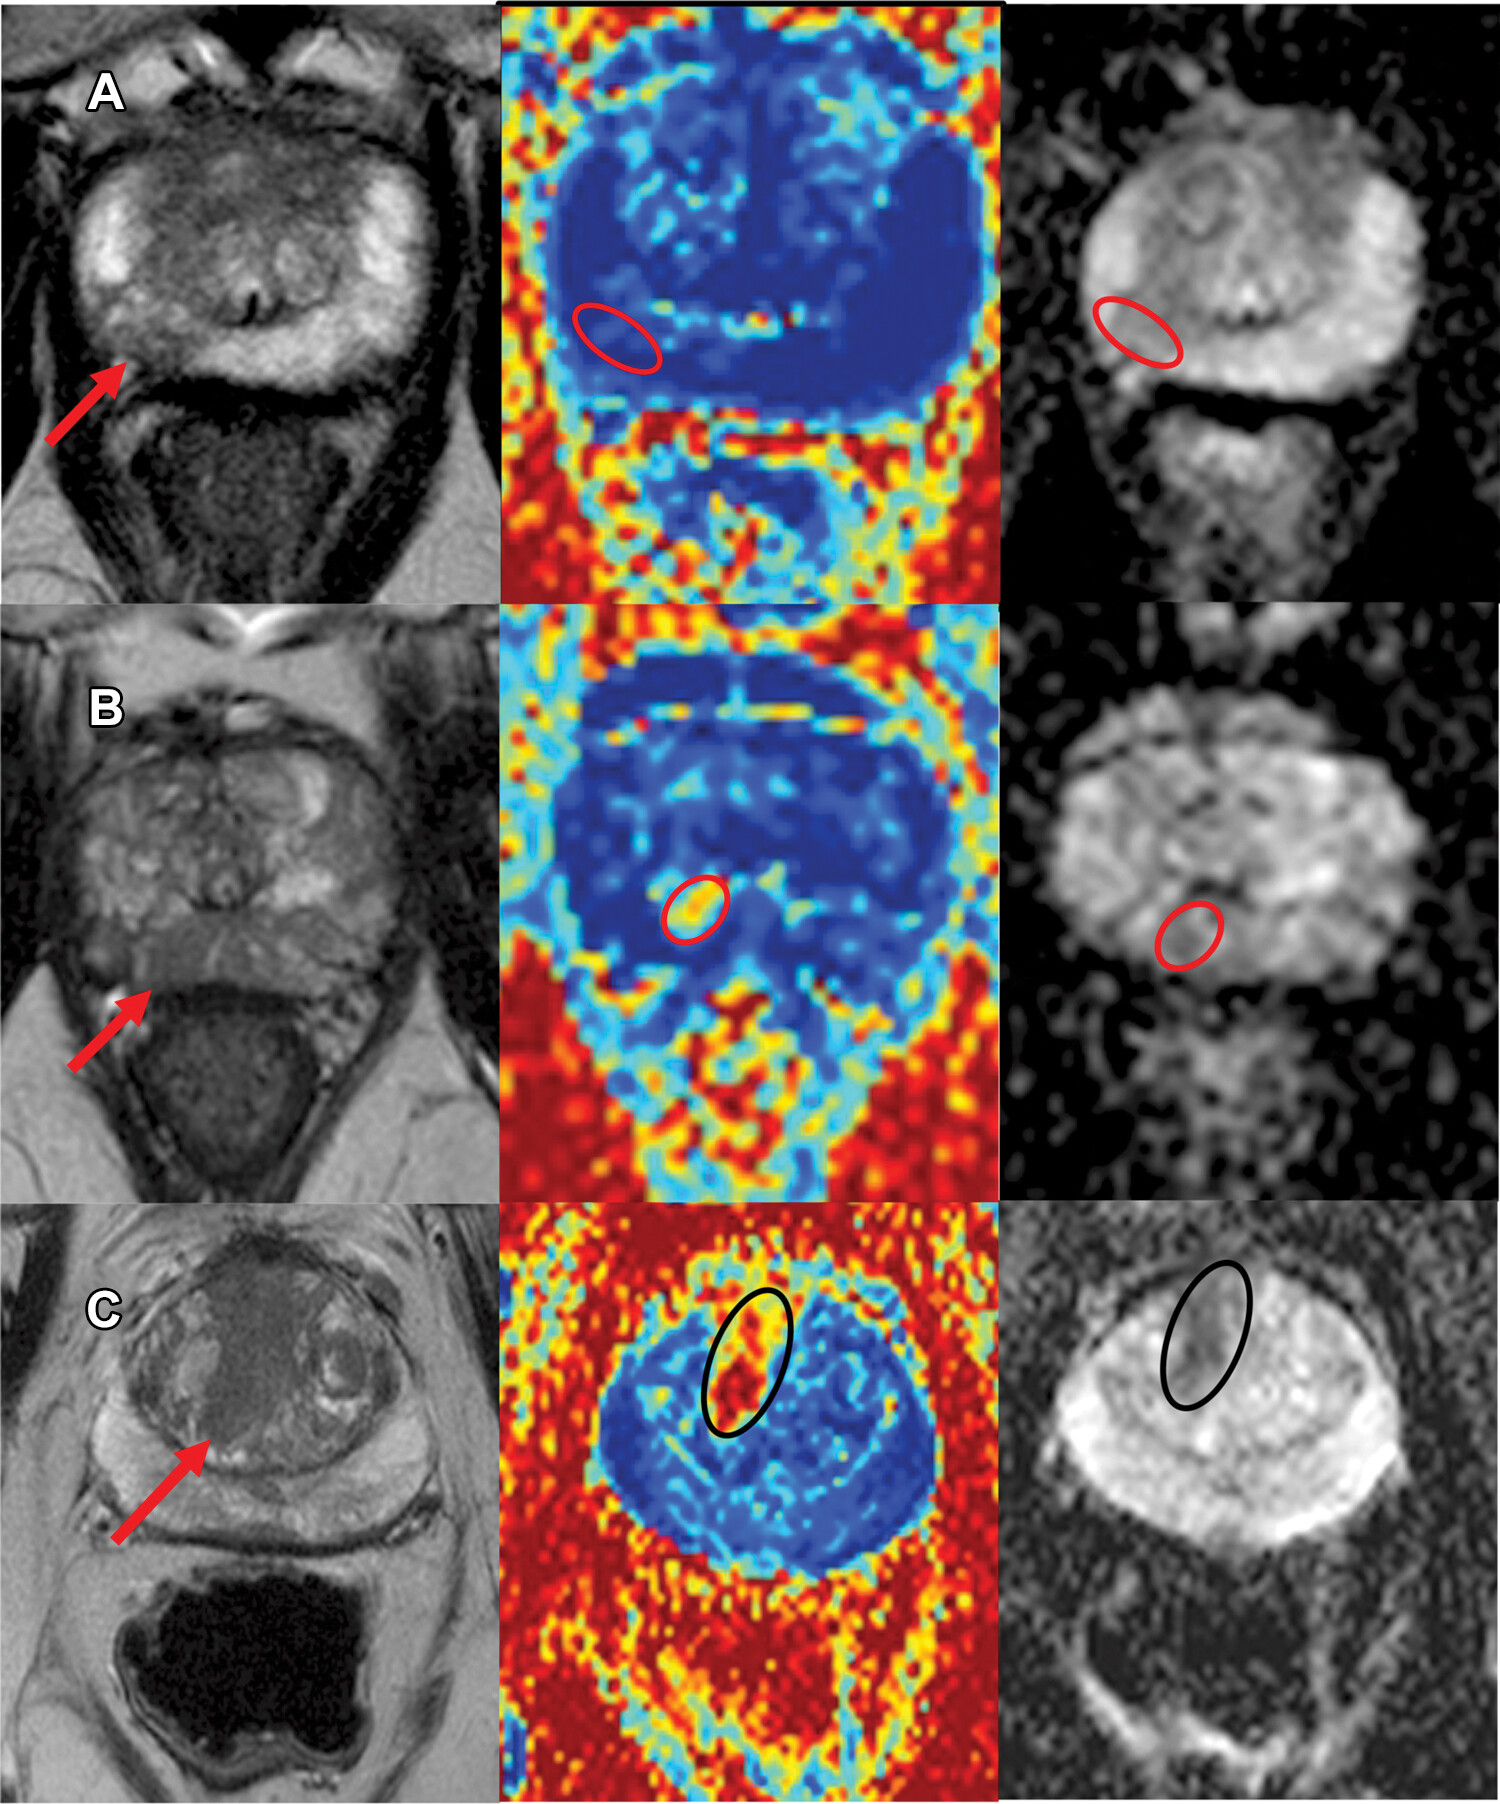

Currently, cancer diagnosis is heavily dependent on histology following invasive biopsy procedures, which can often have severe side effects. In our research, we focus on advanced MRI techniques, which are non-invasive and in-vivo - our work aims to develop computational tools to enhance their discriminatory power.

Our vision is early, accurate and personalised treatment decisions in cancer without the need for uncomfortable and risky biopsies. We use computational modelling and machine learning to design cutting-edge MRI methods to establish new imaging biomarkers and transform patient care. The long-term goal is construction of the next generation of clinical diagnostic tools to replace unnecessary biopsies as the primary diagnostic procedure.